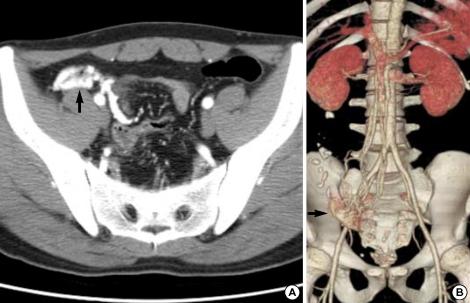

We report on an exceptional vascular cause of gastrointestinal hemorrhage. A 30-yr-old man was admitted because of recurrent hematochezia. Colonoscopy showed circumferential, erythematous, and nodular vascular distensions with hematocystic spots in the terminal ileum resembling varicosis and subsequent computed tomography with 3-dimensional angiographic reconstruction revealed a vascular architecture around the terminal ileum. No other potential source of bleeding was identified. The patient was treated by ileocecectomy and the final diagnosis was of an arteriovenous malformation confined to the terminal ileum. He has been followed up without a further hemorrhagic episode.